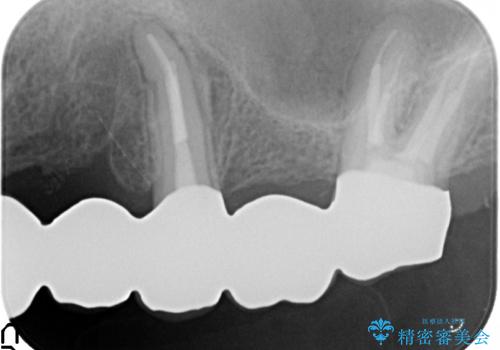

- 歯がない左側でものが咬めず、右側で咬むと歯が痛むので診て欲しいといらっしゃった方の症例です。

根尖病変が認められる歯は再根管治療を行い、歯根が破折していた左上4は抜歯しました。

インプラントは希望されなかったため、左側は1番から7番のロングスパンブリッジによる補綴を行いました。

今回用いたオールセラミッククラウンは、ジルコニアフレームという白い素材の上にセラミックを盛っているため審美性が非常に高いのが特徴です。

またジルコニアは人工ダイヤモンドの材料にも使われているほど高い強度を持っており、そのためオールセラミッククラウンは審美性だけでなく、奥歯やブリッジの補綴も可能とするクラウンです。